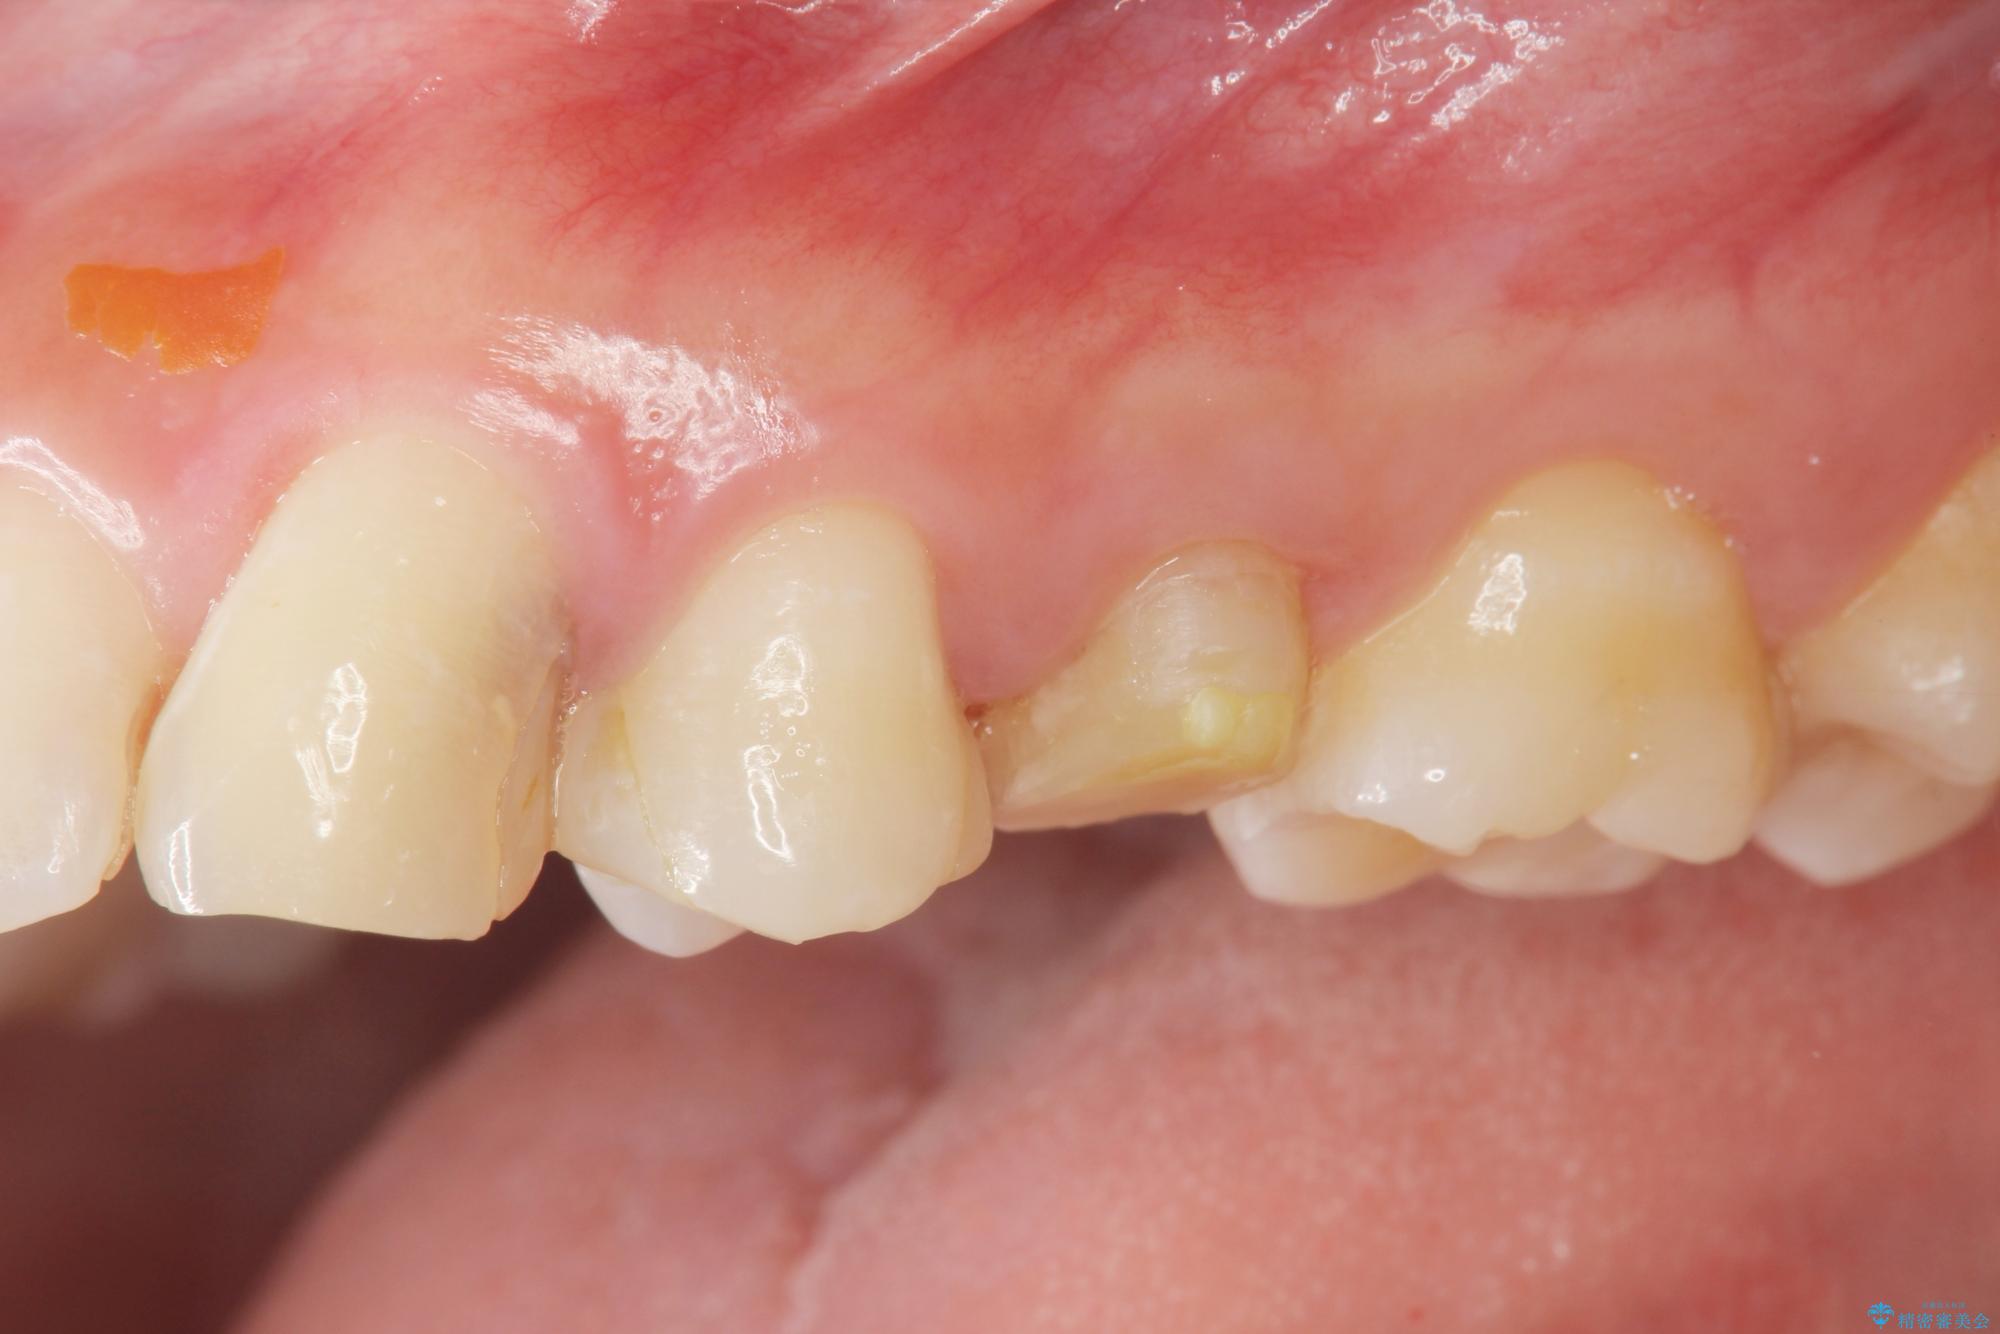

- 歯ぐきの腫れや、歯の内部が黒く見えることからの虫歯の治療を求めて来院されました。

虫歯が大きかったことから、神経の温存はできたものの歯ぐきよりも深い虫歯の問題を解決するため部分矯正治療を併用したセラミック治療を行うこととしました。

当初、歯ぐきよりも深い虫歯のぞんざいや、歯のポジションに問題がありましたがマルチブラケットを用いた部分矯正を行うことで適切な位置へと歯を移動させ、歯周環境を整えたセラミック治療を行うことができました。